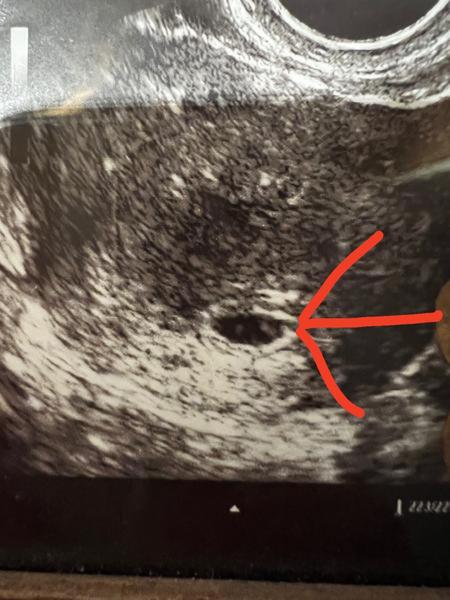

Na fotce, kde směřuje šipka, jedná se o plod (5+1) resp. embryo?

Nebo embryo vychází ze žloutkového váčku, (který tam, si myslím, je vidět)?

šipka ukazuje na typický gestační váček, pravidelného tvaru. Zda lze v něm již detekovat žloutkový váček či embryonální pól z fotografie, říci nedokážu.